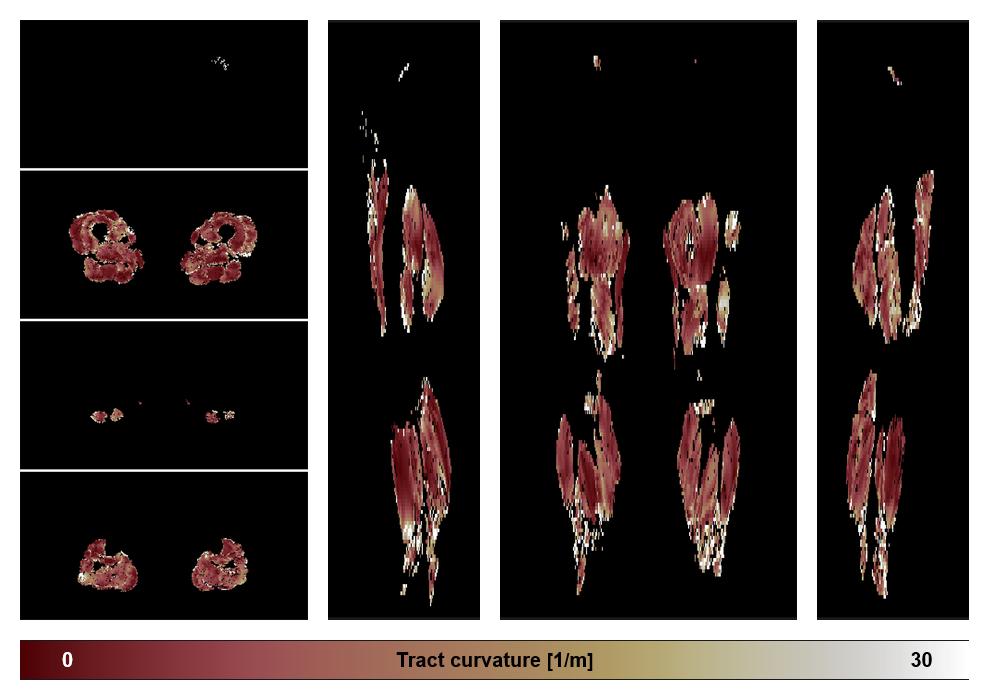

• Muscle fiber curvature map

Muscle fiber tract curvature map based on whole leg DTI based fiber tractography.